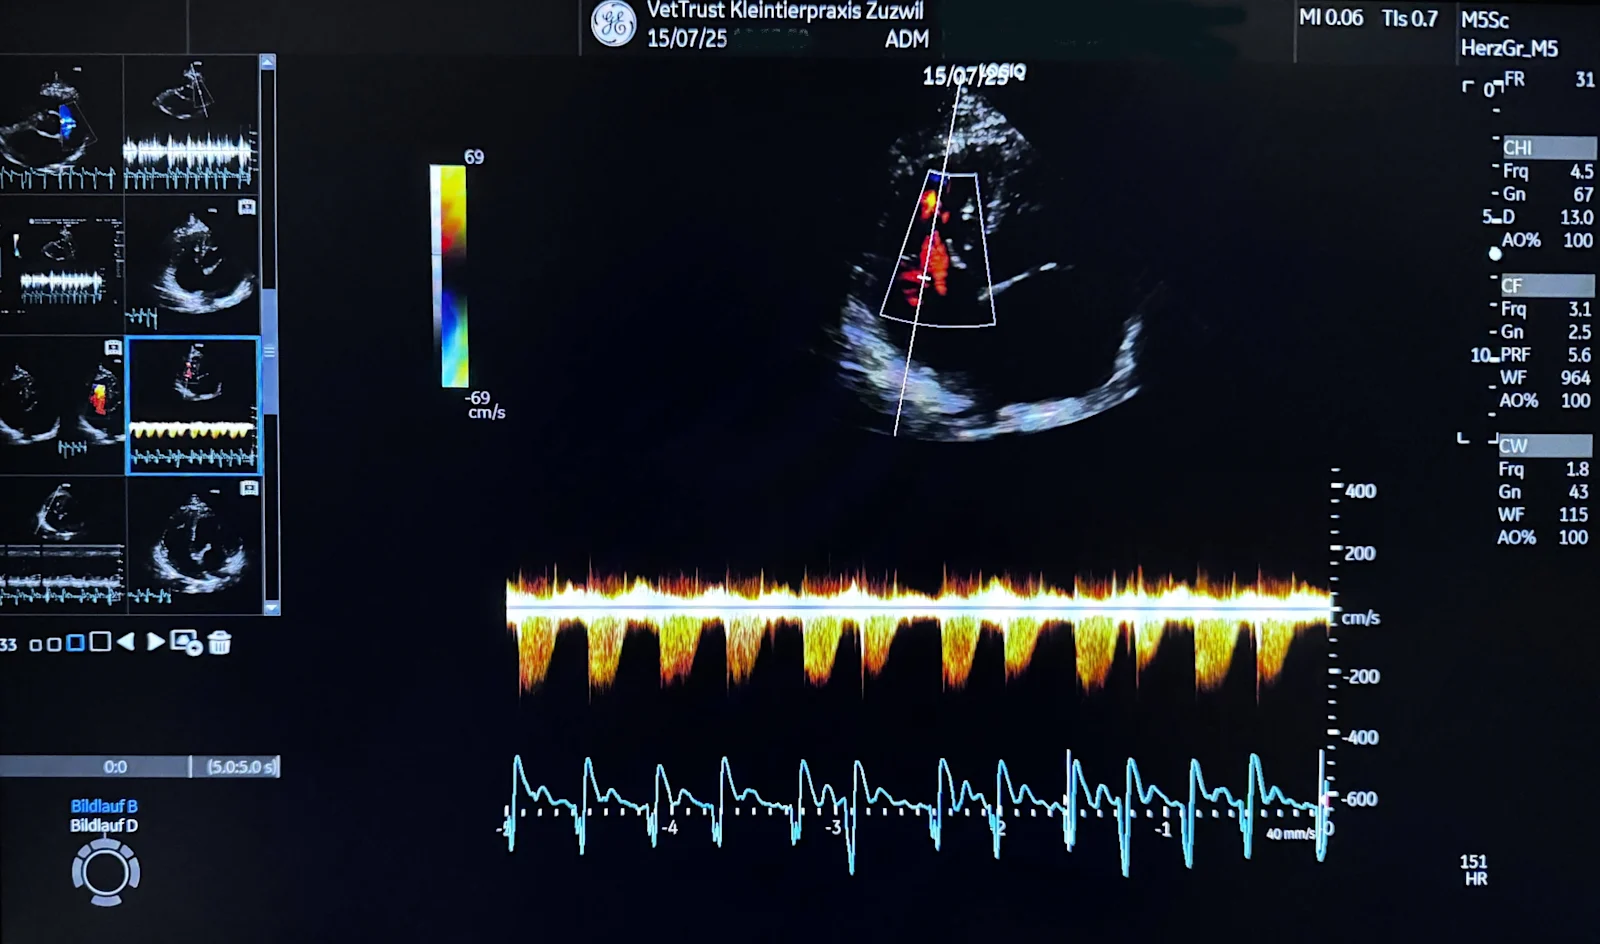

Moderner Herzultraschall: Präzision dank modernster Ausstattung und höchster Expertise von Dr. med. vet. Tanja Rietmann (cand. CAS Cardiology Companion Animals ESAVS, Master of Small Animal Ultrasonography, Tech)

Ein gesundes Herz ist entscheidend für ein langes und aktives Leben unserer Lieblinge. Je früher eine Herzerkrankung behandelt wird, desto besser. Dazu braucht es im besten Fall den Herzultraschall, in der Fachsprache Echokardiografie. Und dazu wiederum braucht es mindestens zwei Dinge: modernste Technik und spezialisierte Fachkompetenz. Bei VetTrust verbinden wir beides und setzen dabei auf moderne Geräte Technologie sowie auf das Wissen unserer hochqualifizierten Spezialisten.

Das Herz ist ein komplexes Organ, das sich ständig in Bewegung befindet. Um kleinste Veränderungen an Herzklappen, Herzmuskulatur und Blutfluss präzise zu erkennen, braucht es ein Gerät mit exzellenter Bildqualität, hoher Rechenleistung, guter Sondenausstattung und modernsten Analysefunktionen, auch KI gestützte.

Wir bei VetTrust bieten an den spezialisierten Standorten Zürich Ost, Basel und Zuzwil (östlich von Wil SG) Echokardiographien (Herzultraschalluntersuchungen) mit verschiedenen Ultraschallsonden an, um vom kleinsten Welpen bis zur grössten Hunderasse, alle qualitativ hochwertig untersuchen zu können.